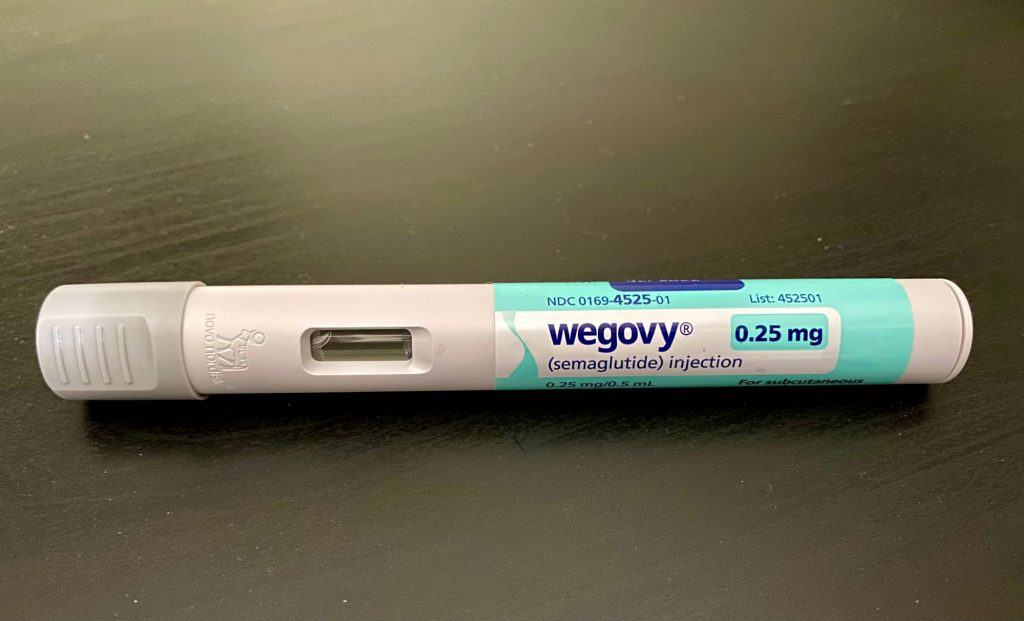

Medicamentos à base de semaglutida e tirzepatida, como Wegovy, Ozempic e Mounjaro, vêm transformando o tratamento da obe...

Ler maisOzempic e Mounjaro podem ampliar desigualdades, dizem cientistas

Medicamentos à base de semaglutida e tirzepatida, como Wegovy, Ozempic e Mounjaro, vêm transformando o tratamento da obe...

Veja os destaques do Olhar Digital News desta terça-feira: EMS anuncia preços da primeira caneta nacional de semaglutida...

Ler maisConfira o Olhar Digital News na íntegra (02/06/2026)

Veja os destaques do Olhar Digital News desta terça-feira: EMS anuncia preços da primeira caneta nacional de semaglutida...